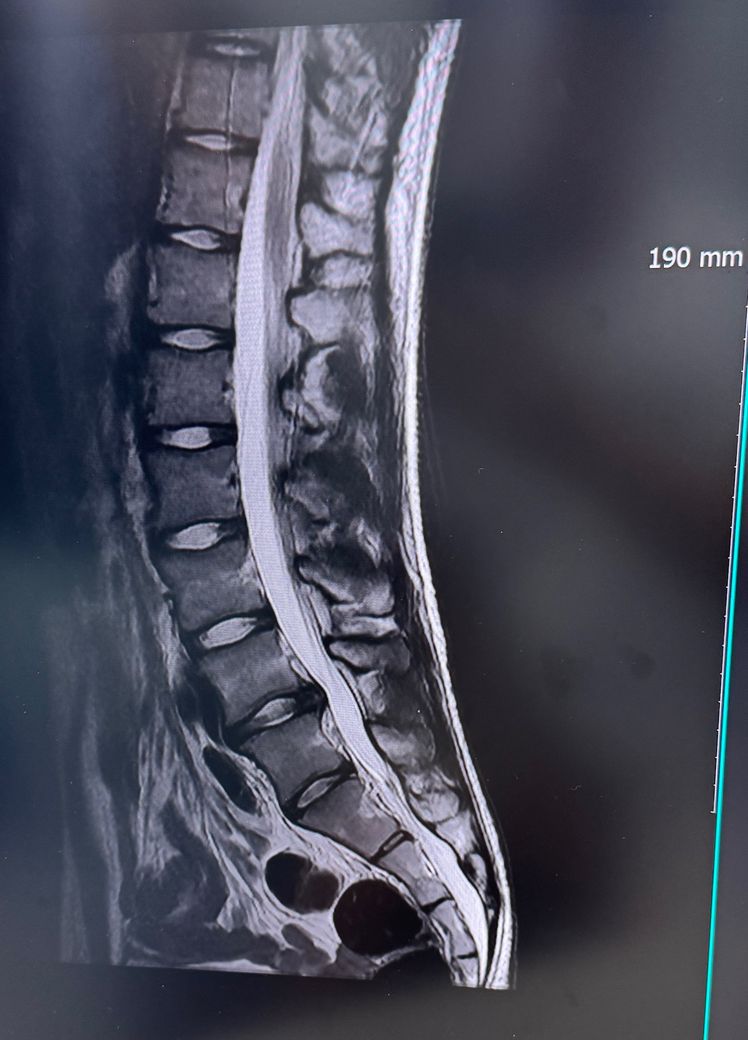

• 1번 째 사진

단면 MRI사진 한장 만으로는 정확한 상태를 파악하기는 어려우며 정확한 상태 검사 및 진료 받아보시고 상태에 맞는 치료 상담 가져보시면 좋을 것으로 생각됩니다.